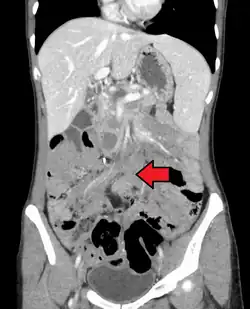

Desmoid tumor as seen on CT scan

Desmoid tumors can occur almost anywhere in the body.[19] They are classified as extra-abdominal, abdominal wall, or intra-abdominal; the last is more common in patients with FAP.[26] Most cases occur in the mesentery, abdominal wall, and extremities.[27] One study has shown extra-abdominal tumors making up 43% of cases, abdominal tumors 49%, and mesenteric 8%, though statistics vary.[16] Pregnancy-related tumors typically arise in the abdominal wall.[28] Tumors located intra-abdominally or in the head and neck have the highest risk of mortality due to the proximity to vital structures.[20]

One analysis has shown a median tumor size of 7.5 cm (3.0 in).[19] Though metastasis cannot occur, the tumors may in some cases be multifocal, with several located in the same body part.[29]